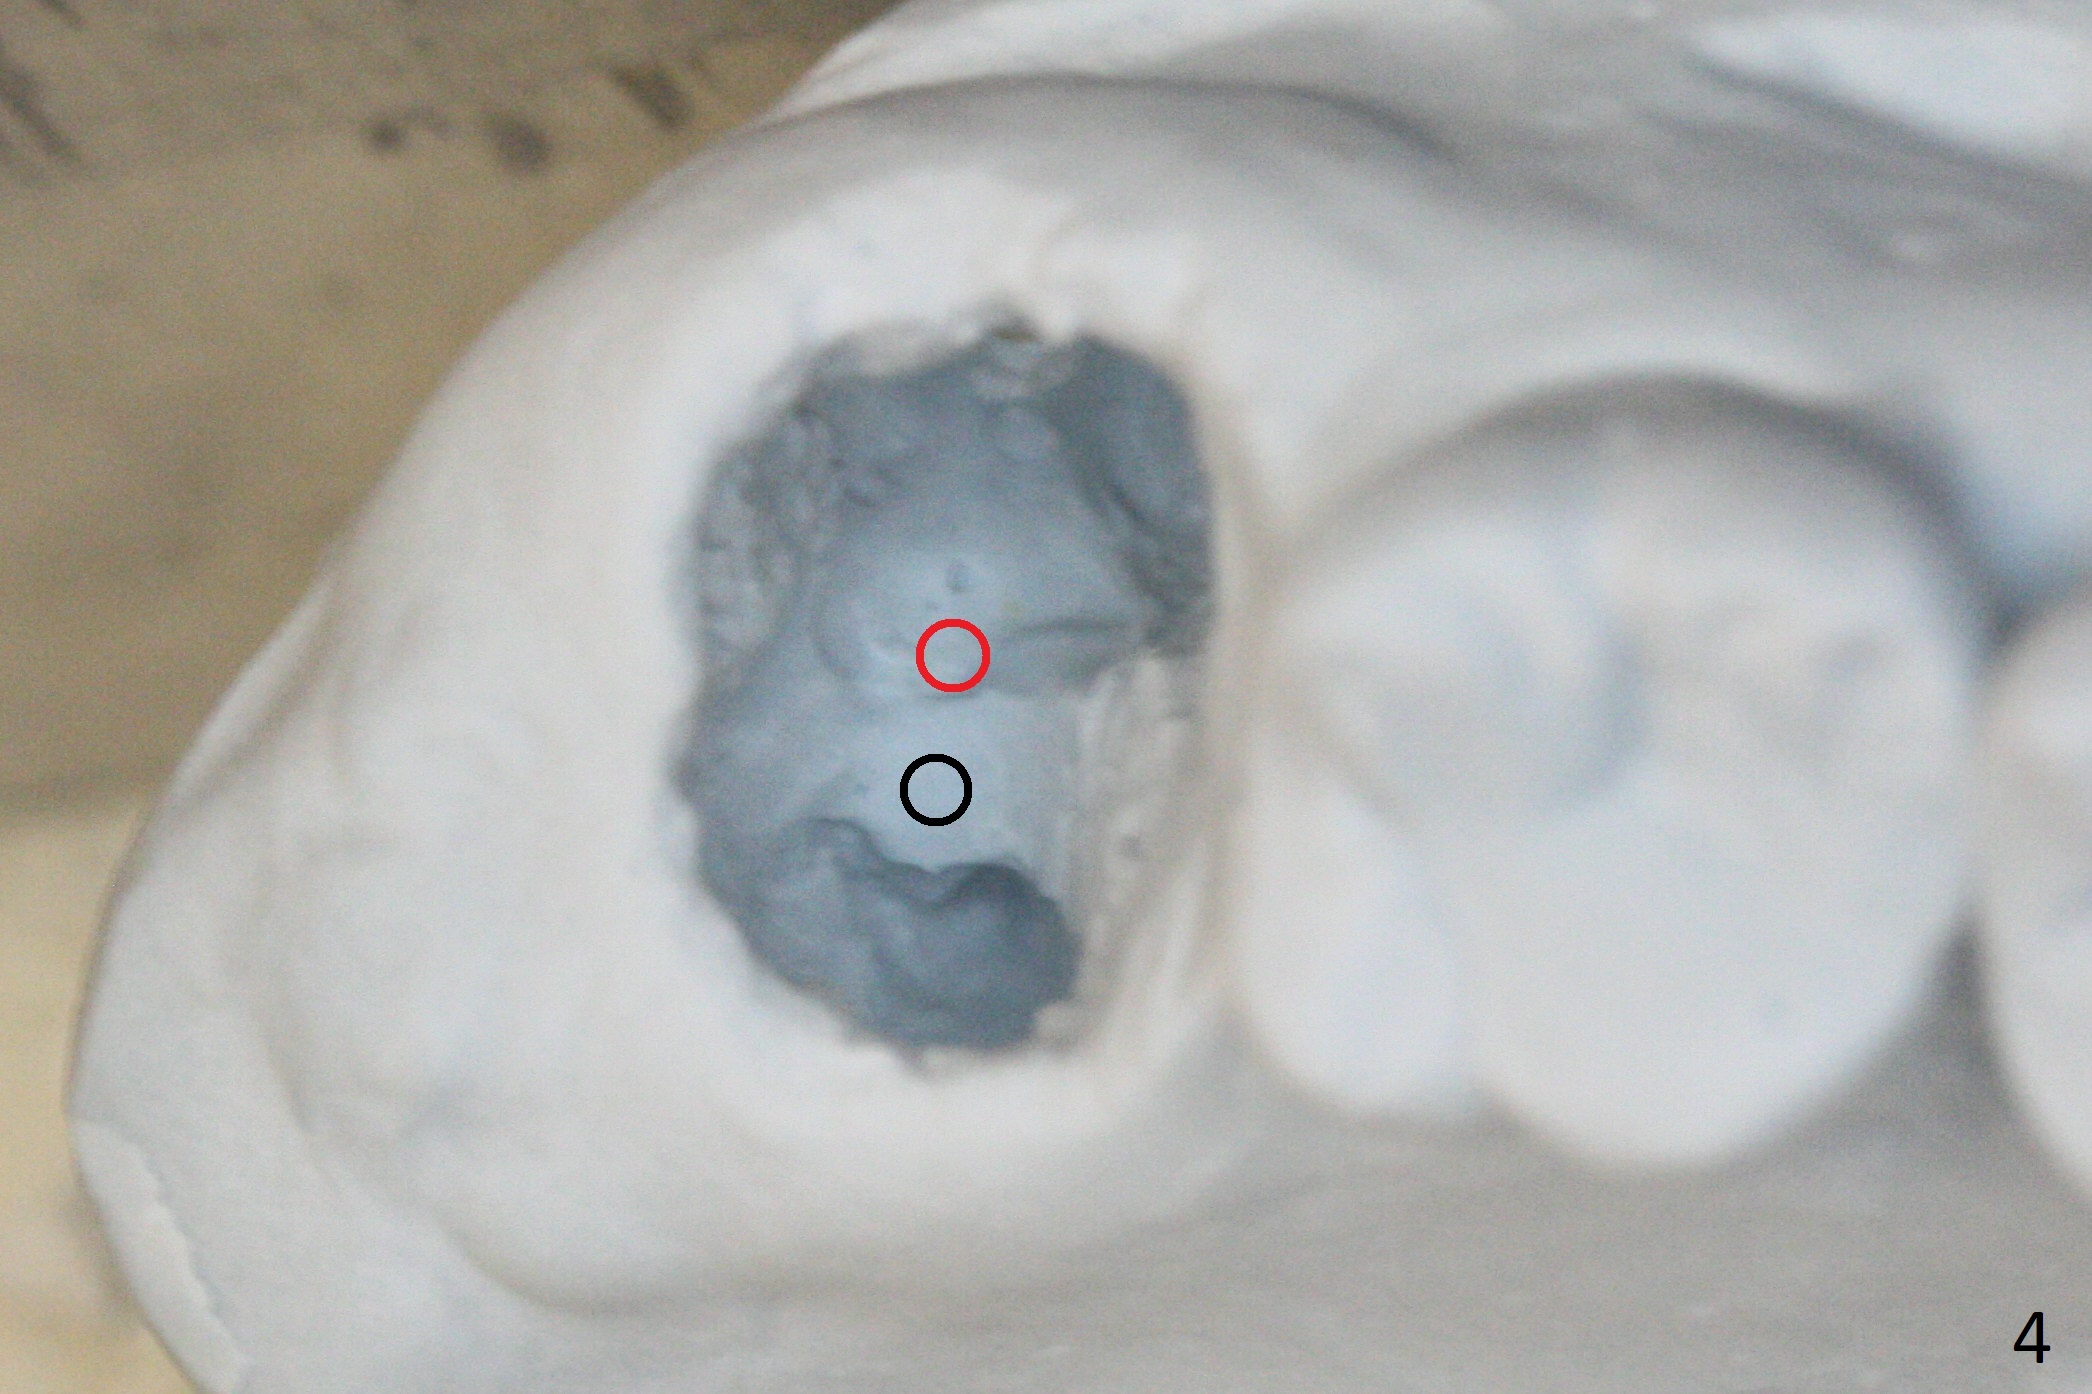

There is a fistula distal to the tooth #2 with deep pocket distopalatally (Fig.1 *), corresponding to palatal root fracture (Fig.2). There is a septum (Fig.3 S) between the buccal (B) and palatal (P) sockets. Osteotomy is initiated in the center of the septum (Fig.4 black circle). In fact the center of the socket is buccal (red circle), in which osteotomy should have been established because of the presence of the distopalatal bony defect associated with the root fracture and the distal fistula. The less ideal initial osteotomy leads to palatal placement of the implant and abutment (Fig.11 vs. 12).

Fig.5 shows the mesial slope of the socket (M), which is more or less the center of the socket mesiodistally. If the osteotomy were set up in the red circle (Fig.6) in the mesial slope (Fig.8 green dashed line), the trajectory of 4.5x11 mm dummy implant (Fig.7) would be more ideal (Fig.8 red outline) with more native bone contact. Finally a longer IBS implant is placed (4.5x15 mm, Fig.9,10) to achieve primary stability (50 Ncm). When the provisional is removed for impression 3 months 10 days postop, the implant is found to have been placed distopalatally (Fig.13), which should have been avoided. It appears essential to use guide for a distal implant. It is agonizing to re-encounter the off-axial implant (Fig.14) and the distopalatal access hole (Fig.15) 1 year post cementation. It is also amazing that the abutment screw has not loosened. A fair-sized piece of bone graft has just been removed buccally (Fig.15,16). The patient complains of sensitivity 2 years 3 months post cementation, although there is no abnormality around the implant crown. Guided surgery is essential to avoid restoration complication. There is no thread exposure nearly 3 years post cementation; in fact the apical portion of the abutment is covered by the bone (Fig.17,18).